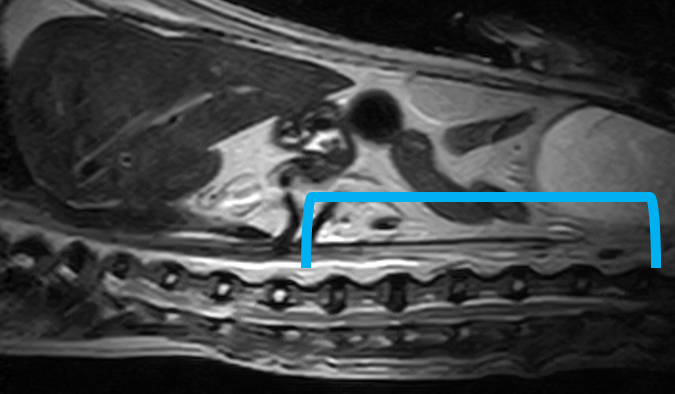

W obrębie kanału kręgowego najczęstszymi wskazaniami do badania rezonansem magnetycznym u zwierząt są:

• ocena przepukliny i stopnia ucisku na rdzeń kręgowy

• dyskopatie, neuropatie, radikulopatie

• zwyrodnieniowe zwężenie lędźwiowe krzyżowe (DLSS)

• spondylomielopatia szyjna

• malformacje Chiariego

• wady złącza czaszkowo mózgowego